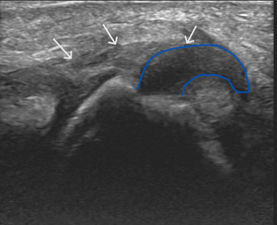

Long axis ultrasound of the thumb at the level of the metacarpophalangeal joint.

The white arrows demonstrate the adductor pollicis aponeurosis. The blue trace outlines the torn and retracted ULC from the base of the proximal phalanx. It has flipped proximally – lying superficial to the aponeurosis.